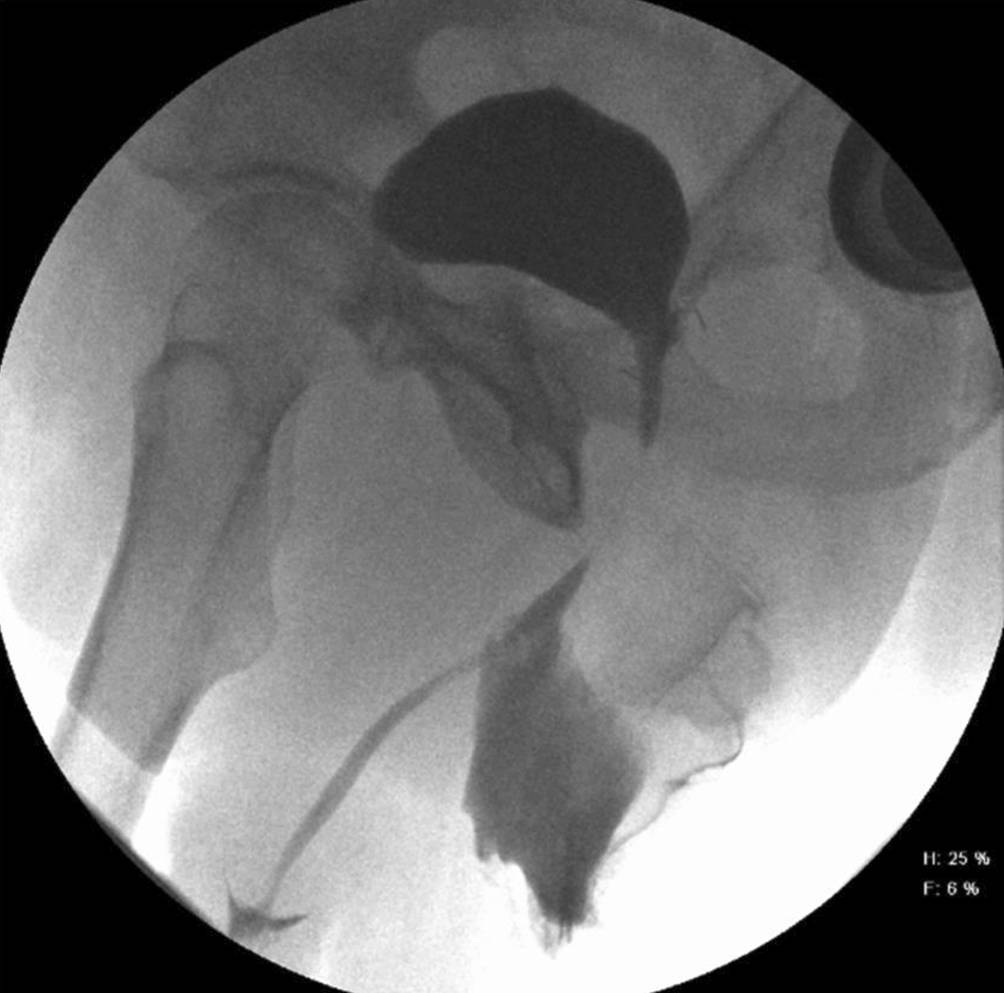

Vesikourethrale Anastomosenstriktur nach radikaler Prostatektomie

Bei Patienten nach radikaler Prostatektomie ist die Striktur der vesikourethralen Anastomose eine glücklicherweise seltene, jedoch schwerwiegende Komplikation. Es bestehen keine klaren Richtlinien für das therapeutische Vorgehen. Falls mehrmalige endourologische Eingriffe zu keiner Rezidivfreiheit führen, sollte über ein offenes oder laparoskopisch-chirurgisches Verfahren nachgedacht werden. Die Evidenzlage ist relativ schmal angelegt und zeichnet sich durch lediglich eine eingeschränkte Anzahl an retrospektiven, monozentrischen Studien oder limitierten Fallserien aus. Die Wahl der Therapie muss also umso mehr in Absprache mit dem Patienten und unter Berücksichtigung individueller Präferenzen erfolgen.

Ein erstes Therapieschema zur Behandlung der Anastomosenstrikturen wurde von Giudice et al. [16] vorgeschlagen. Noch knapp passierbare Strikturen wurden, im Gegensatz zu komplett obliterierten, zuerst einer Form der endourologischen Therapie zugeführt, wobei erst nach einem allfälligen, zweiten Rezidiv eine offene Operation erfolgte. Bei den offenen Eingriffen muss man sich der Konsequenzen des Zugangs bewusst sein. In Analogie zu den Harnröhrenrekonstruktionen nach Beckentrauma mit Abriss der Urethra erfolgt der Zugang perineal – wie bei der Anlage einer bulboprostatischen Anastomose. Das narbige Areal muss dabei komplett reseziert und anschliessend eine Reanastomosierung der Harnröhre an den Blasenhals erfolgen. Hierbei muss über den Beckenboden zugegangen werden, und eine Läsion des Sphincter urethrae externus mit konsekutiver, drittgradiger Belastungsinkontinenz ist meist unumgänglich. Obwohl die langfristige Offenheitsrate bei über 90 % liegt, ist die Implantation eine artifiziellen Sphinktersystems die im Verlauf logische und notwendige Konsequenz [42]. Ein artifizieller Sphinkter ermöglicht, nach zwischenzeitlich langer Leidensgeschichte aufgrund der rezidivierenden Strikturen, jedoch die Wiederherstellung eines durchgängigen unteren Harntraktes mit ungestörter und „willkürlich“ gesteuerter Miktion via naturalis. Es sind jedoch auch die Möglichkeit offener abdominaler Zugänge oder laparoskopisch-roboterassistierter Verfahren (intra- und extraperitoneal) beschrieben [23, 26, 37]. Sogar die Verwendung von Mundschleimhaut zur Beseitigung der verengten vesikourethralen Anastomose wurde kürzlich als potenziell neuartiges Verfahren präsentiert [43]. Vor allem die abdominalen, roboterassistierten Verfahren scheinen bezüglich der Inkontinenz ein deutlich besseres Outcome zu erzielen. Diese funktionellen Resultate müssen sich in grösseren Kohorten und prospektiv angelegten Studien aber zuerst noch bewahrheiten. Als letzte Möglichkeit kann den Patienten, quasi als Ultima Ratio, eine der alternativen Formen der Harnableitung angeboten werden (suprapubischer Katheter, Ileumconduit oder katheterisierbarer Nabelpouch).